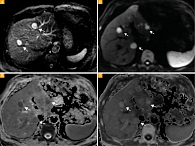

Рис. 4. Форма роста метастазов увеальной меланомы в печень: красная стрелка – инфильтративная форма роста, белая стрелка – узловая форма; DIXON (William Thomas Dixon technique) out of phase (А, Б); Т2-ВИ – коронарная плоскость (В)

Мы предположили у двух пациентов инфильтративный характер роста метастазов в синусоидальном пространстве, а у остальных девяти — узловой в перипортальной области. Предположения сделаны на основе локализации, очертаний и форм образований, в соответствии с гистологической классификацией моделей роста метастазов УМ H.E. Grossniklaus.

Сопоставляя результаты наших исследований с гипотезой H.E. Grossniklaus, мы определили у двух из десяти пациентов инфильтративный характер метастазов, а у остальных восьми – узловой. У одного нашего пациента в одной доле печени наблюдались разные модели роста метастазов (рис. 4). На основании анализа данных МР-исследований в динамике мы предположили, что узловой и инфильтративный характер метастазов – это стадии единого метастатического процесса.